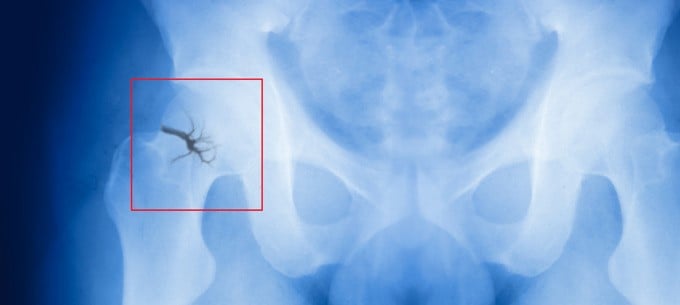

The hip labrum is a ring of cartilage that sits on the outer rim of your hip joint socket. It acts as a cushion and secures the femoral head in the socket. Running can cause your hip labrum to tear.

Symptoms include a catching, clicking or locking sound when you move your hip, a reduced range of motion and stiffness. However, not all labral tears produce symptoms.

A labral tear can be diagnosed by a physical examination alongside other tests, such as an MRI scan or X-ray. Your doctor may also suggest an injection of anaesthesia — if this relieves your hip pain then you likely don’t have a labral tear but another problem in the hip joint.

You can treat your labral tear by taking over-the-counter NSAIDs and performing daily physiotherapy exercises. You may also need steroid injections. In more severe cases, where these treatments aren’t successful, your doctor may recommend you have a keyhole surgery called arthroscopy.